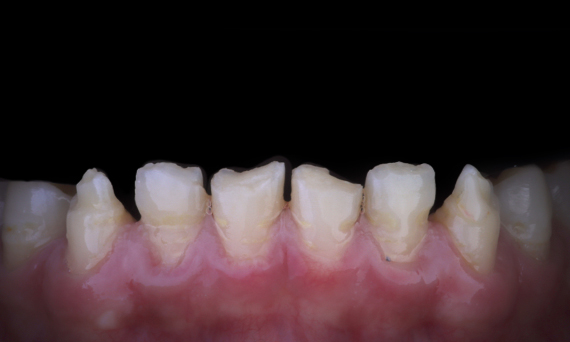

Aesthetic Rehabilitation of Amelogenisis Imperfecta

CEREC Tessera

An esthetic rehabilitation in the anterior region could be realized with labside CEREC Tessera restorations veneered with Celtra Ceram.

Before: The treatment objective was to rehabilitate the anterior maxilla and mandible for esthetic improvement. The clinical diagnosis revealed ameloenesis imperfecta.

After: Labside- fabricated restoration made from advanced lithium-disilicate ceramic CEREC Tessera and for the high esthetic result, the veneering with Celtra Ceram.

Sabine Mayer (CDT)

Koblenz, Germany

Mario Pace (CDT)

Lahnstein, Germany